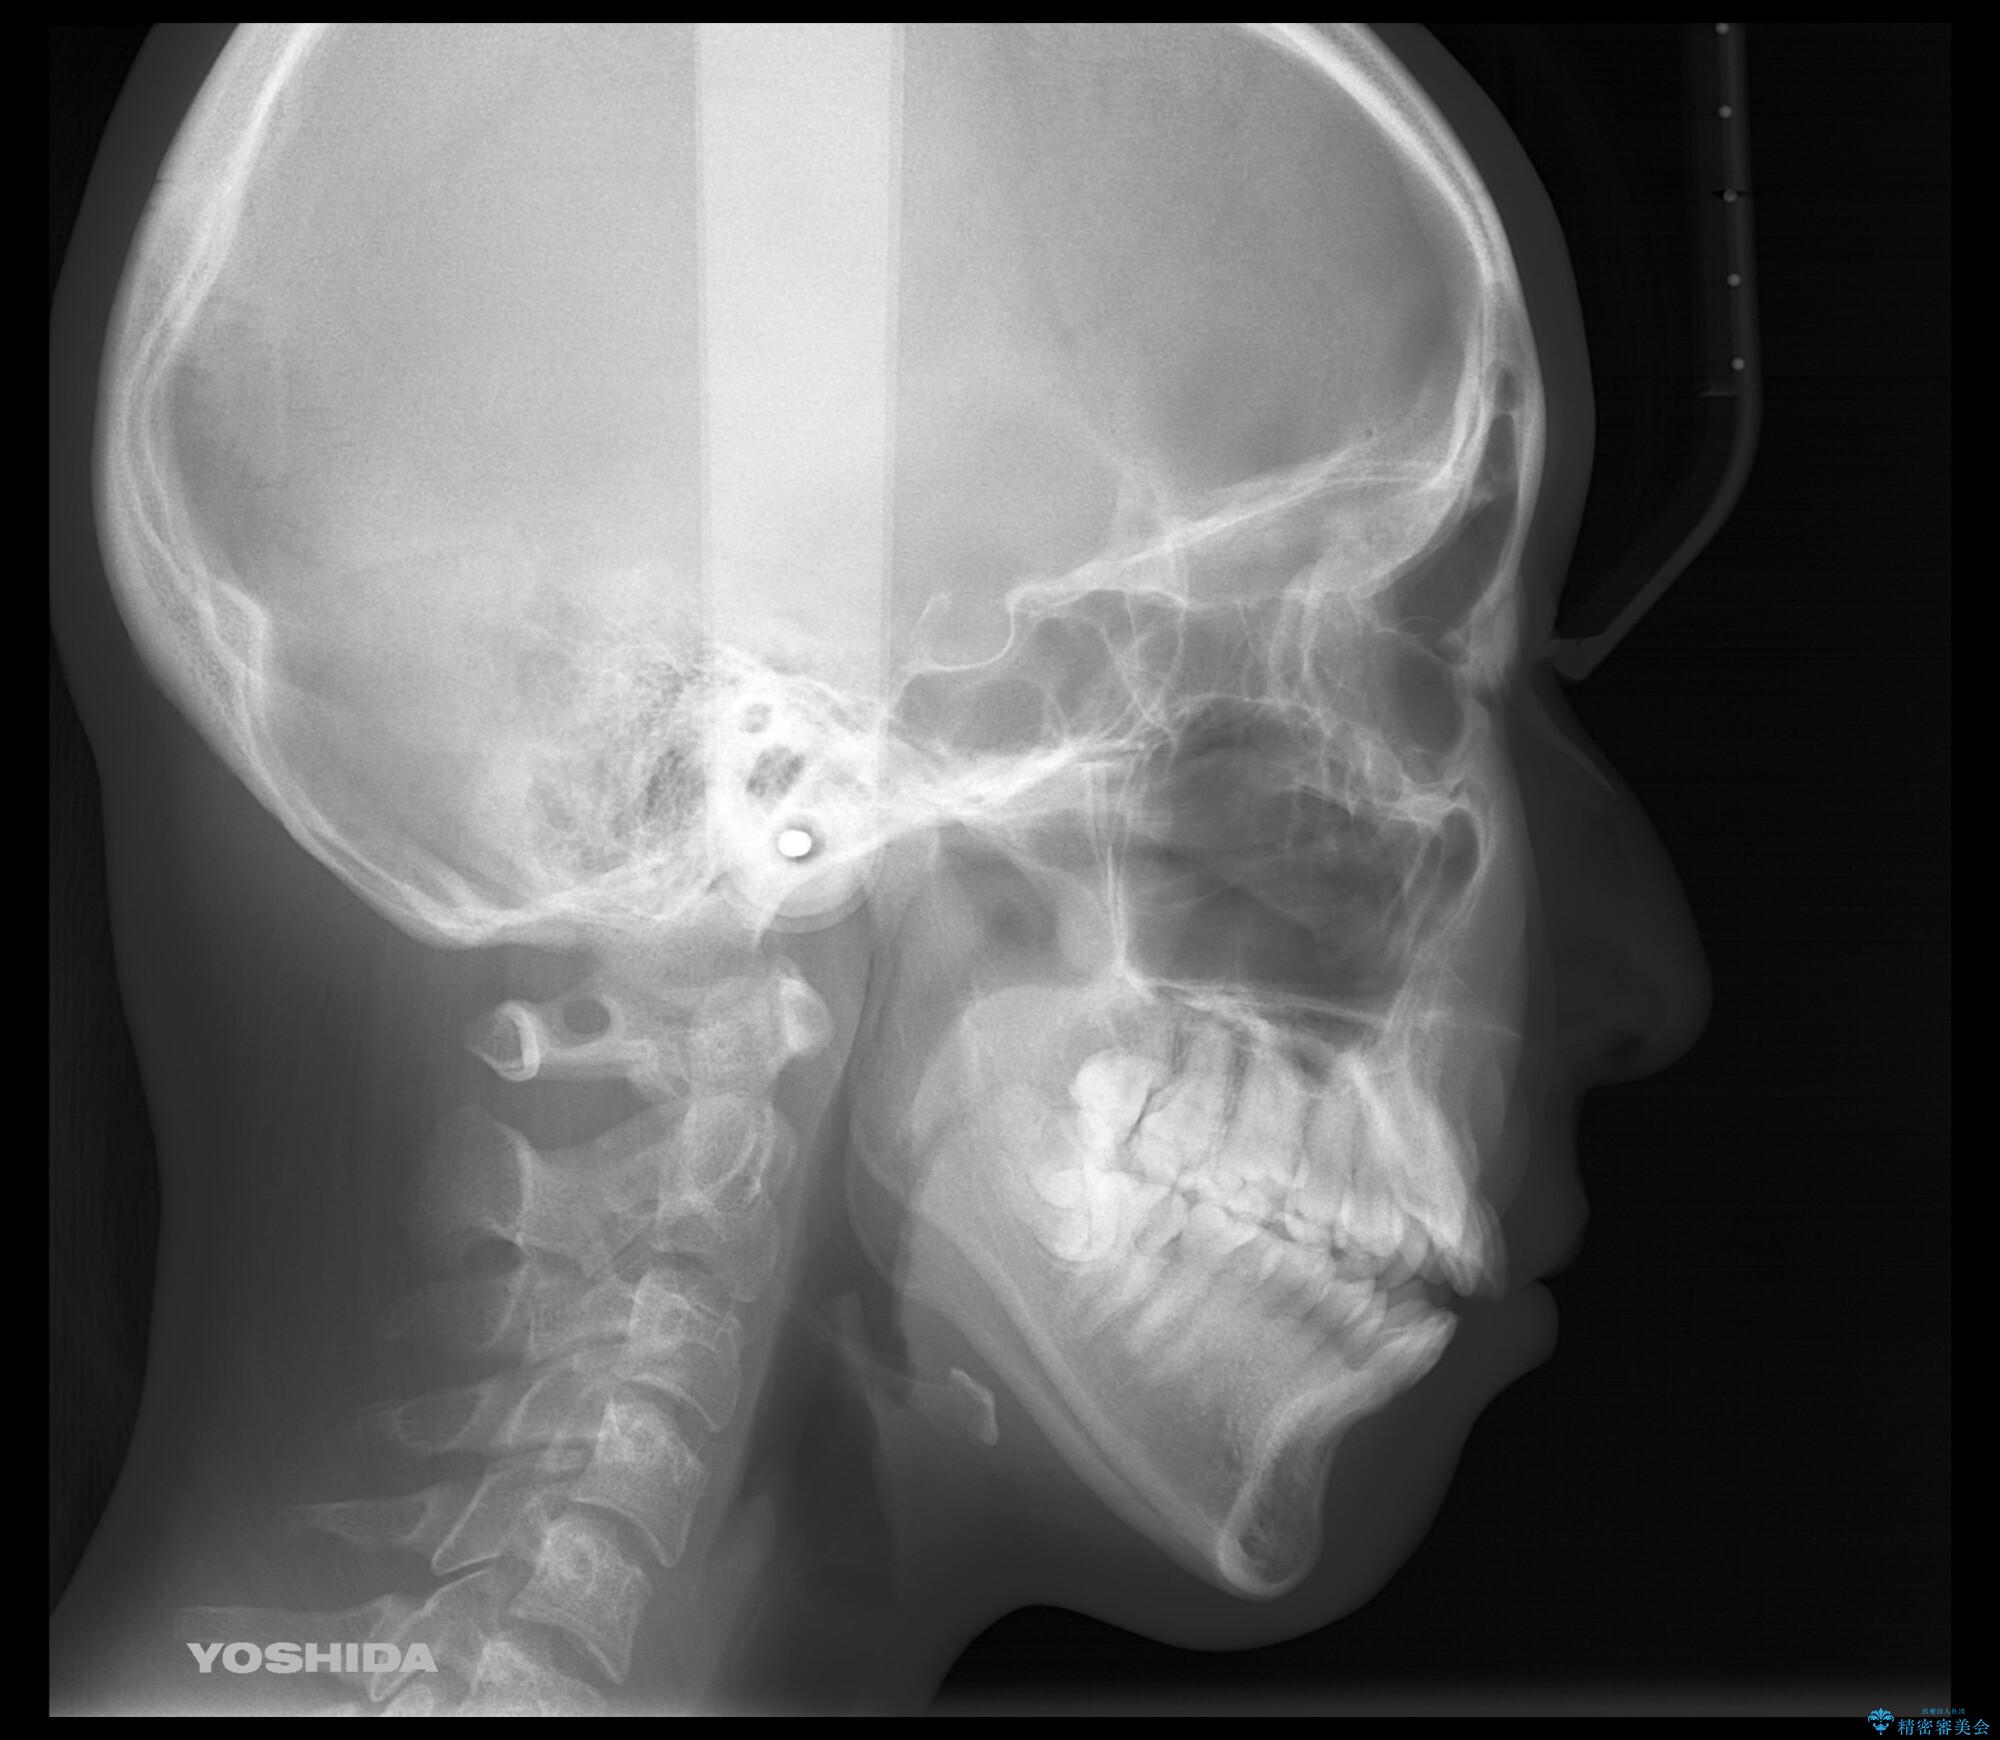

- 前歯のがたつきが気になるとご相談にいらした患者様です。矯正検査の結果、骨格的なズレが大きかったため当初の治療計画では外科矯正をご案内しました。ご本人が手術を望んでおらず、可能な限りの改善を目指すことを目標に治療を開始しました。

元々の骨格的なズレが大きかったため、当初は外科矯正をご提案していました。患者様の強いご希望により、非外科的な処置のみで可及的な改善を目指すことを目標に治療を行いました。以前よりもしっかり噛めるようになり、見た目も劇的に改善したことで大変ご満足いただけました。